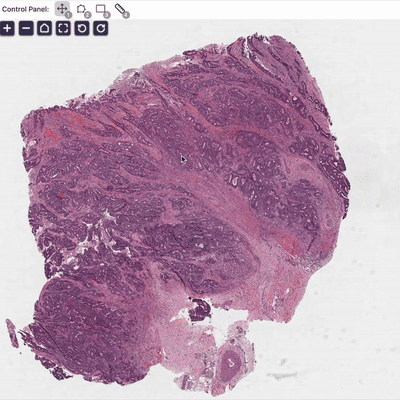

1. Foundation Model for Pathology

Pathology is medicine's ground truth. We train AI models with vision, language, and knowledge to improve machine understanding of pathology.

A pathologist–AI collaboration framework for enhancing diagnostic accuracies and efficiencies

Zhi Huang, Eric Yang, Jeanne Shen, Dita Gratzinger, ..., Thomas J. Montine & James Zou

Nature Biomedical Engineering (2024), cover article

nuclei.io: AI platform for digital pathology [website] []

Artificial Intelligence Reveals Features Associated with Breast Cancer Neoadjuvant Chemotherapy Responses from Multi-stain Histopathologic Images

Zhi Huang, et al.

NPJ Precision Oncology (2023)

✨ AI-powered prediction of breast cancer treatment outcomes from H&E and IHC.